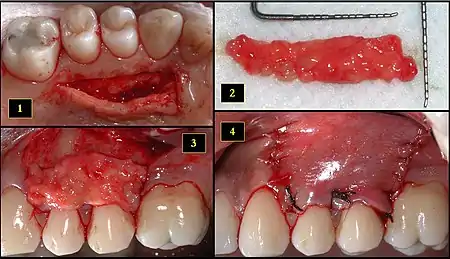

1. Recipient site exhibits gingival recession on both premolars and first molar (molar recession is not an esthetic issue and will not be treated)

2. Incisions prior to flap reflection

3. Full thickness flap elevated

4. Another viewpoint of the flapped recipient site

1. Ipsilateral palatal mucosa serving as the donor site

2. The retrieved connective tissue, approximately 25 × 6 mm in dimension

3. Connective tissue placed at recipient site

4. Recipient site flap coronally advanced and sutured to entirely cover the graft